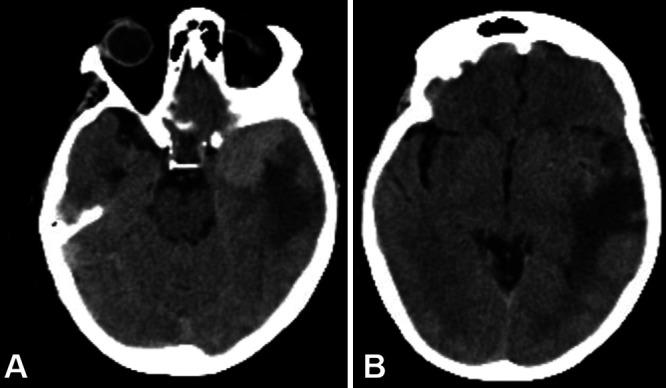

This is the second reported case of an intrameningioma abscess without a clear source of infection, occurring in a 70-year-old female with a history of transsphenoidal craniopharyngioma resection and radiation many years prior. She presented with severe fatigue and altered mental status initially ascribed to adrenal insufficiency, and magnetic resonance imaging showed a new heterogeneously enhancing left temporal mass with surrounding edema. After urgent tumor resection, pathology demonstrated a World Health Organization grade II meningioma (radiation induced). After a course of steroids and intravenous nafcillin, the patient recovered without neurological deficits.

这是第二例报道的无明确感染源的脑膜瘤内脓肿病例,发生在一名70岁女性身上,该女性多年前有经蝶窦颅咽管瘤切除术和放疗史。她最初表现为严重疲劳和精神状态改变,最初归因于肾上腺功能不全,磁共振成像显示左侧颞叶有一个新的不均匀强化肿块并伴有周围水肿。紧急肿瘤切除术后,病理显示为世界卫生组织II级脑膜瘤(放疗诱发)。经过一个疗程的类固醇和静脉注射萘夫西林治疗后,患者康复,无神经功能缺损。